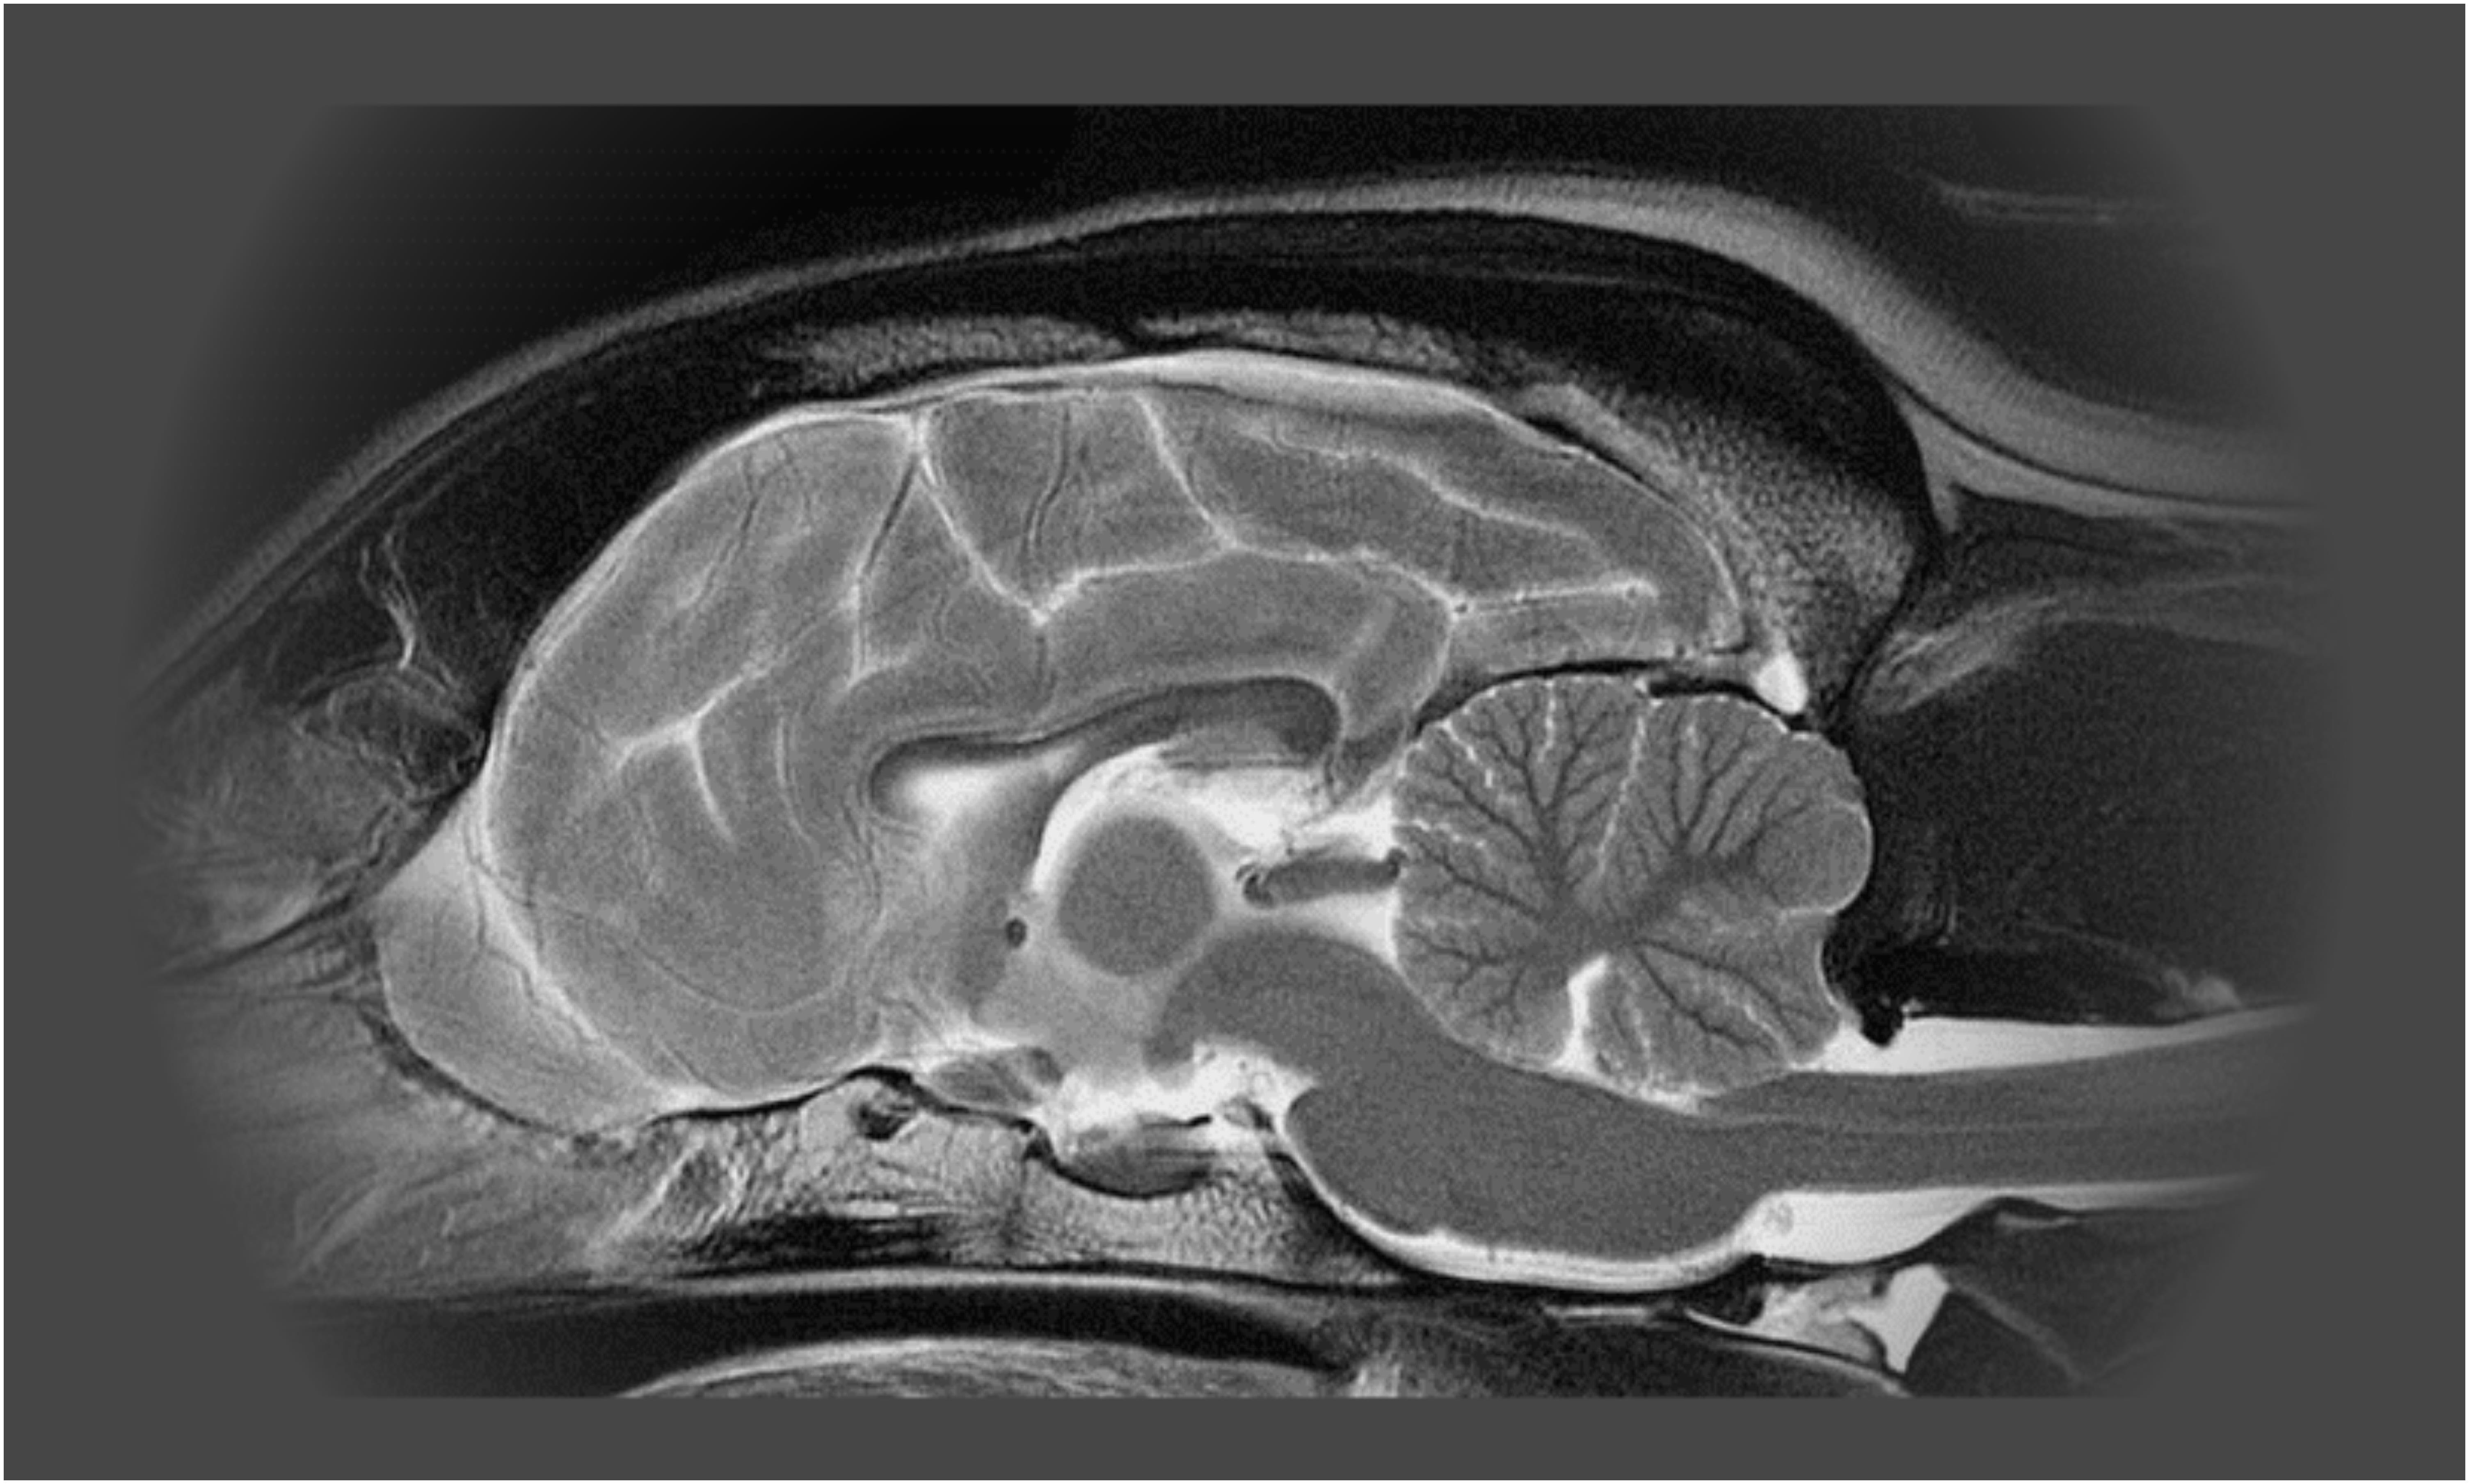

Mozog psaEpilepsia je chronické ochorenie mozgu, ktoré sa prejavuje opakovaným výskytom nekontrolovateľných záchvatov. Na základe aktuálnych štatistík sa predpokladá, že touto chorobou sú postihnuté asi  4% psov. Epilepsia sa ani u zvierat nedá celkom vyliečiť, pomocou liekov sa dá len „kontrolovať“. Typ zvolenej terapie závisí od typu epilepsie a jej úspešnosť (za úspešnú sa považuje už liečba, pri ktorej počet záchvatov klesne o 50%) závisí aj od dôslednosti dodržiavania pokynov veterinára. Pes s epilepsiou musí byť doživotne kontrolovaný.